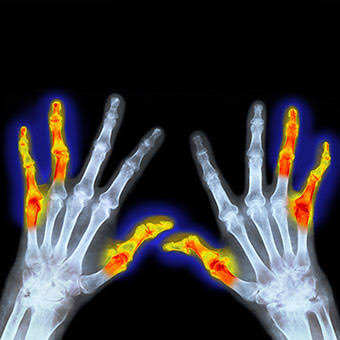

类风湿关节炎,其主要的病理基础是滑膜的改变,当滑膜出现了类风湿滑膜炎改变以后,会逐渐的破坏掉关节腔内的软骨,导致关节间隙的狭窄和关节的粘连,严重的影响患者的生活质量,很多人因为手部的变形甚至筷子都拿不了。

类风湿性关节炎的患者早期通常会表现出明显的晨僵,尤其是表现在手部。很多患者会在早期的时候表现出早上起来的时候,手指的僵硬感,握不拢,而且握拳的时候会有疼痛,通常需要经过30分钟左右的时间才能缓解。

当然当很多患者已经到了晚期,关节已经出现了明显的变形,从相关的查体以及x光片子,也可以明确患者是否存在类风湿性的关节炎。从下图您仔细看就会看出正常的手与类风湿性关节炎手部的骨骼改变。

另外类风湿这种疾病也会导致患者出现比较严重的骨质疏松,建议类风湿患者一定要做双能x线检查,明确自己是否存在骨质疏松,或者说骨质疏松到了什么样的程度,根据结果进行系统的抗骨质疏松治疗。